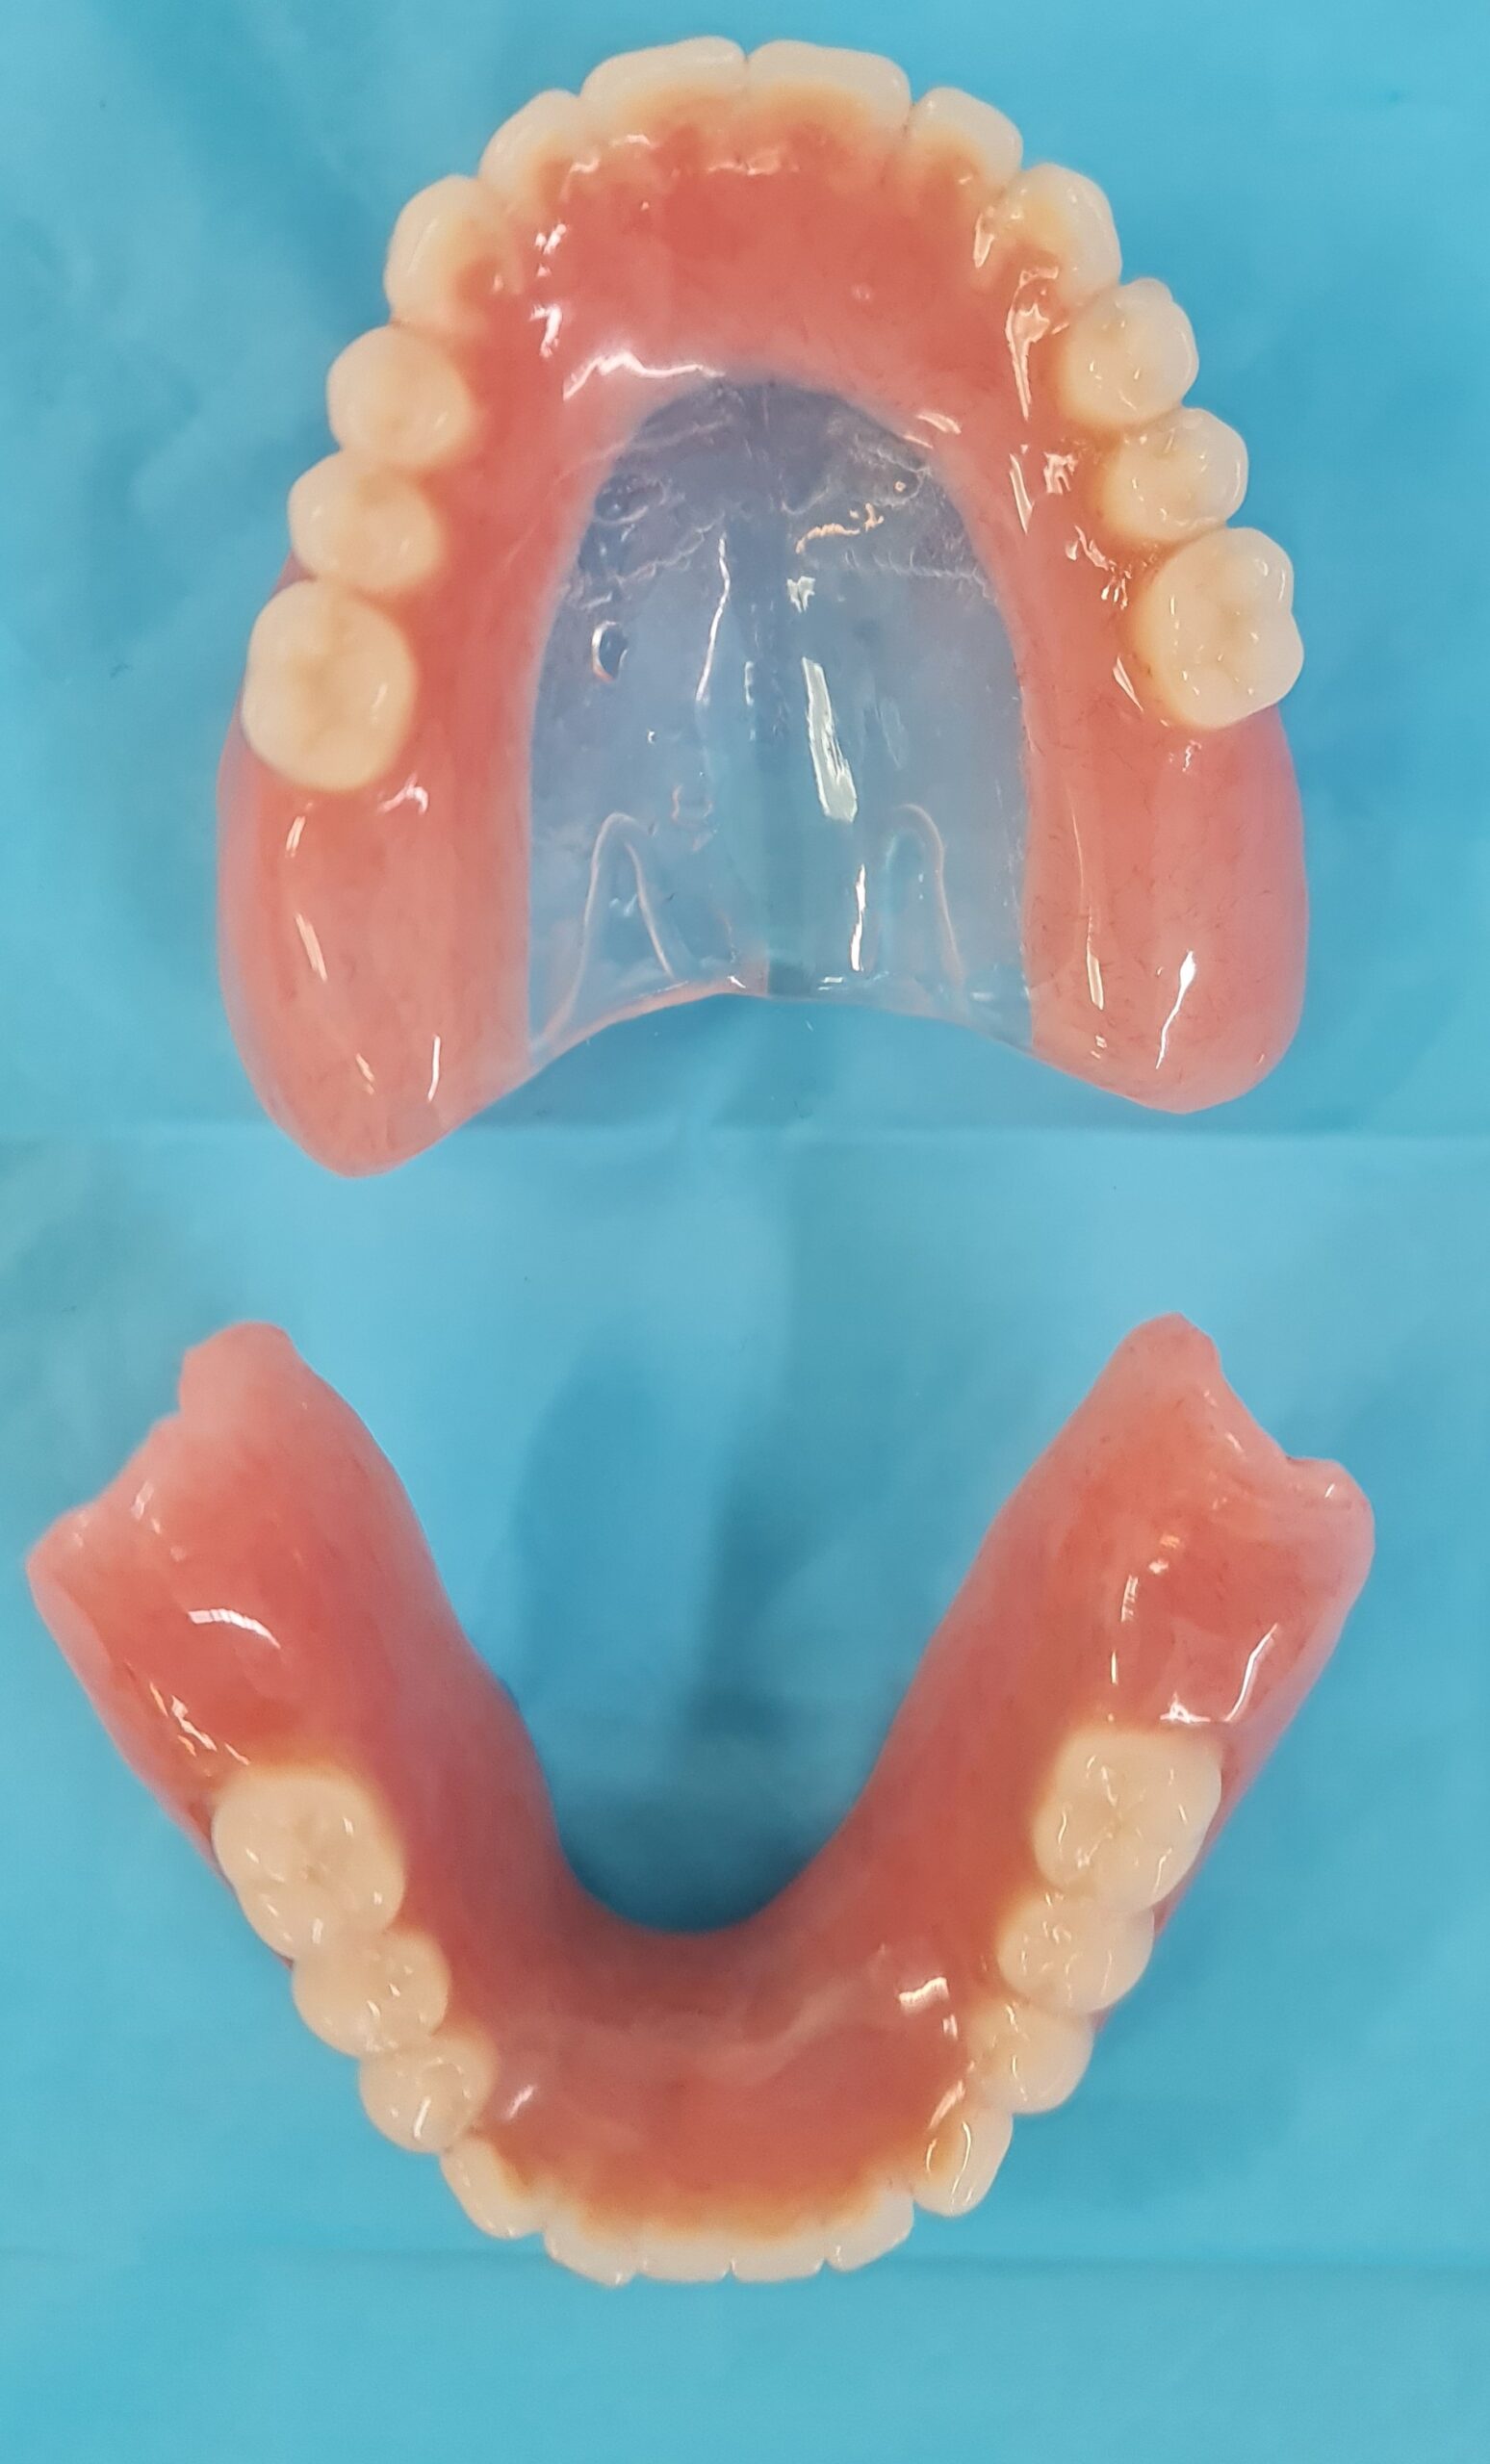

Compromise Option Upper and Lower Jaw Implant Overdentures

There are two types of implant dentures: bar-retained and ball-retained. In both cases, the denture will be made of an acrylic base that will look like gums. Porcelain or acrylic teeth that look like natural teeth are attached to the base. Both types of dentures need at least two implants for support.

Upper Jaw Implant Complete Dentures